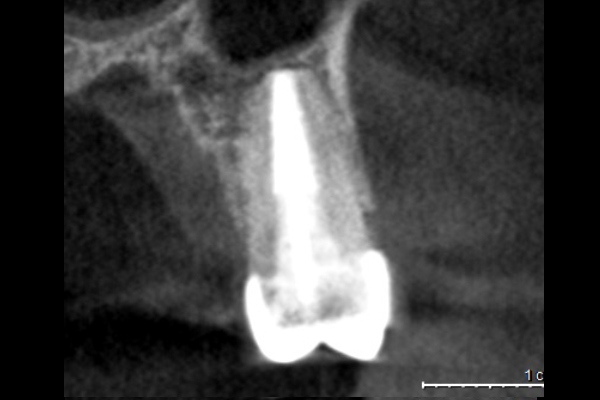

40代男性の大臼歯(奥歯)の症例

- 主訴

- 「時々歯茎が腫れる」とのことでご来院されました。数週間前から症状があり、他の医院では「抜歯の可能性がある」と言われ、不安に感じていらっしゃいました。

- 期間

- 治療期間2ヶ月、治療回数3回、レントゲン写真で治癒を確認できるまでの期間6ヶ月

- 治療内容

- 1.古い被せ物の除去と虫歯の徹底除去

まず、古い銀歯を外し、内部に広がっていた虫歯を丁寧に取り除きました。

2.マイクロスコープ下での根管治療

唾液などによる細菌の侵入を防ぐ「ラバーダム」を装着し、マイクロスコープ(歯科用顕微鏡)で根管内を数十倍に拡大しながら治療を進めました。複雑な形状の根管の内部まで、汚染された組織を徹底的に洗浄・消毒します。

3.根管充填(こんかんじゅうてん)

根管内が完全にクリーンになったことを確認し、再感染を防ぐために専用の薬剤で隙間なく密閉しました。

4.土台と被せ物の作製

歯の強度を補うための土台を立て、最終的なセラミックの被せ物を作製し、装着しました。

- 治療に伴うリスク

- 少しでも汚染物質が残ると再発のリスクが高まります。